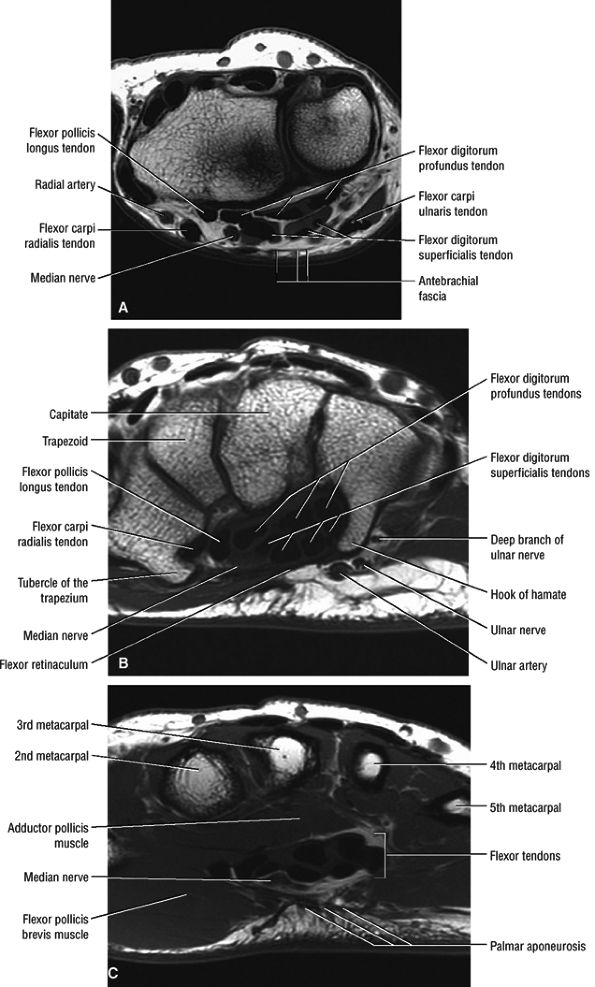

The antebrachial fascia proximal to the wrist (Fig. 12.37A)

-

The transverse carpal ligament proper (Fig. 12.37B)

The palmar aponeurosis between the thenar and hypothenar muscles (Fig. 12.37C)

FIGURE 12.37 ● Normal MR anatomy of the median nerve. (A) Axial T1-weighted image at the level of the distal radioulnar joint demonstrates the antebrachial fascia overlying the median nerve. (B) Axial T1-weighted image at the level of the distal carpal tunnel shows the flexor retinaculum extending between the hook of the hamate and the tubercle of the trapezium. (C) Axial T1-weighted image at the level of the proximal metacarpals shows the palmar aponeurosis and the proximal digital branches of the median nerve.